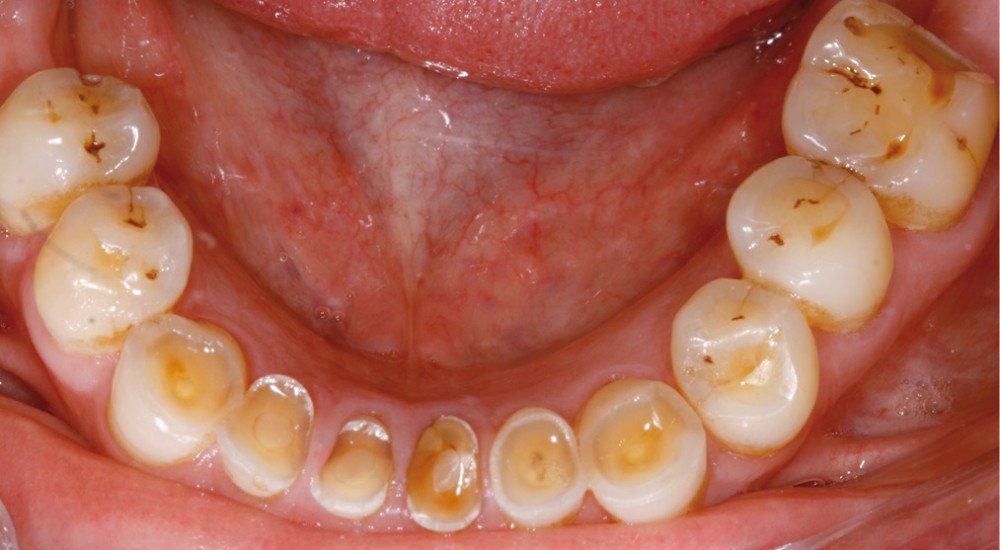

Examen clinique (fig. 1-6)

• L’examen intrabuccal montre de nombreux édentements non compensés (14, 15, 16, 24, 25, 26, 27, 47 et 36) ainsi que des pertes de substance très importantes, notamment dans le secteur antérieur.

Une attrition sévère, couplée à une occlusion sans calage postérieur, a engendré des difficultés pour s’alimenter.